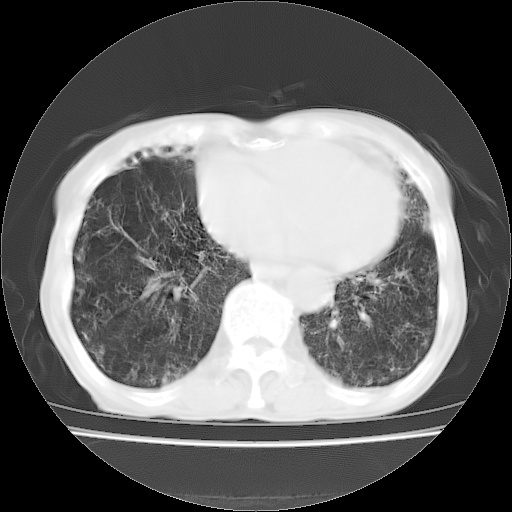

病人发热、气促就诊。原二周前已行ct扫描,当时诊断为双肺下叶、右肺中叶支气管扩张并感染,双肺上叶片状渗出性病变。今天复查胸部ct,双肺下叶支气管扩张并感染病灶较前明显吸收,但双肺上叶渗出性病变较范围较前明显增大。

现传今天ct图像给大家讨论。

双肺感染性病变,不排除机遇性肺炎。双下肺间质纤维化较明显。

双肺间质广泛纤维化,上叶炎症考虑特异性感染,例如念珠菌,克雷伯杆菌什么的,建议实验室检查。

肺内广泛感染并间质纤维化,牵拉性支气管扩张

双肺多发大片状、斑片状高密度渗出影,部分实变,考虑病毒性肺炎。